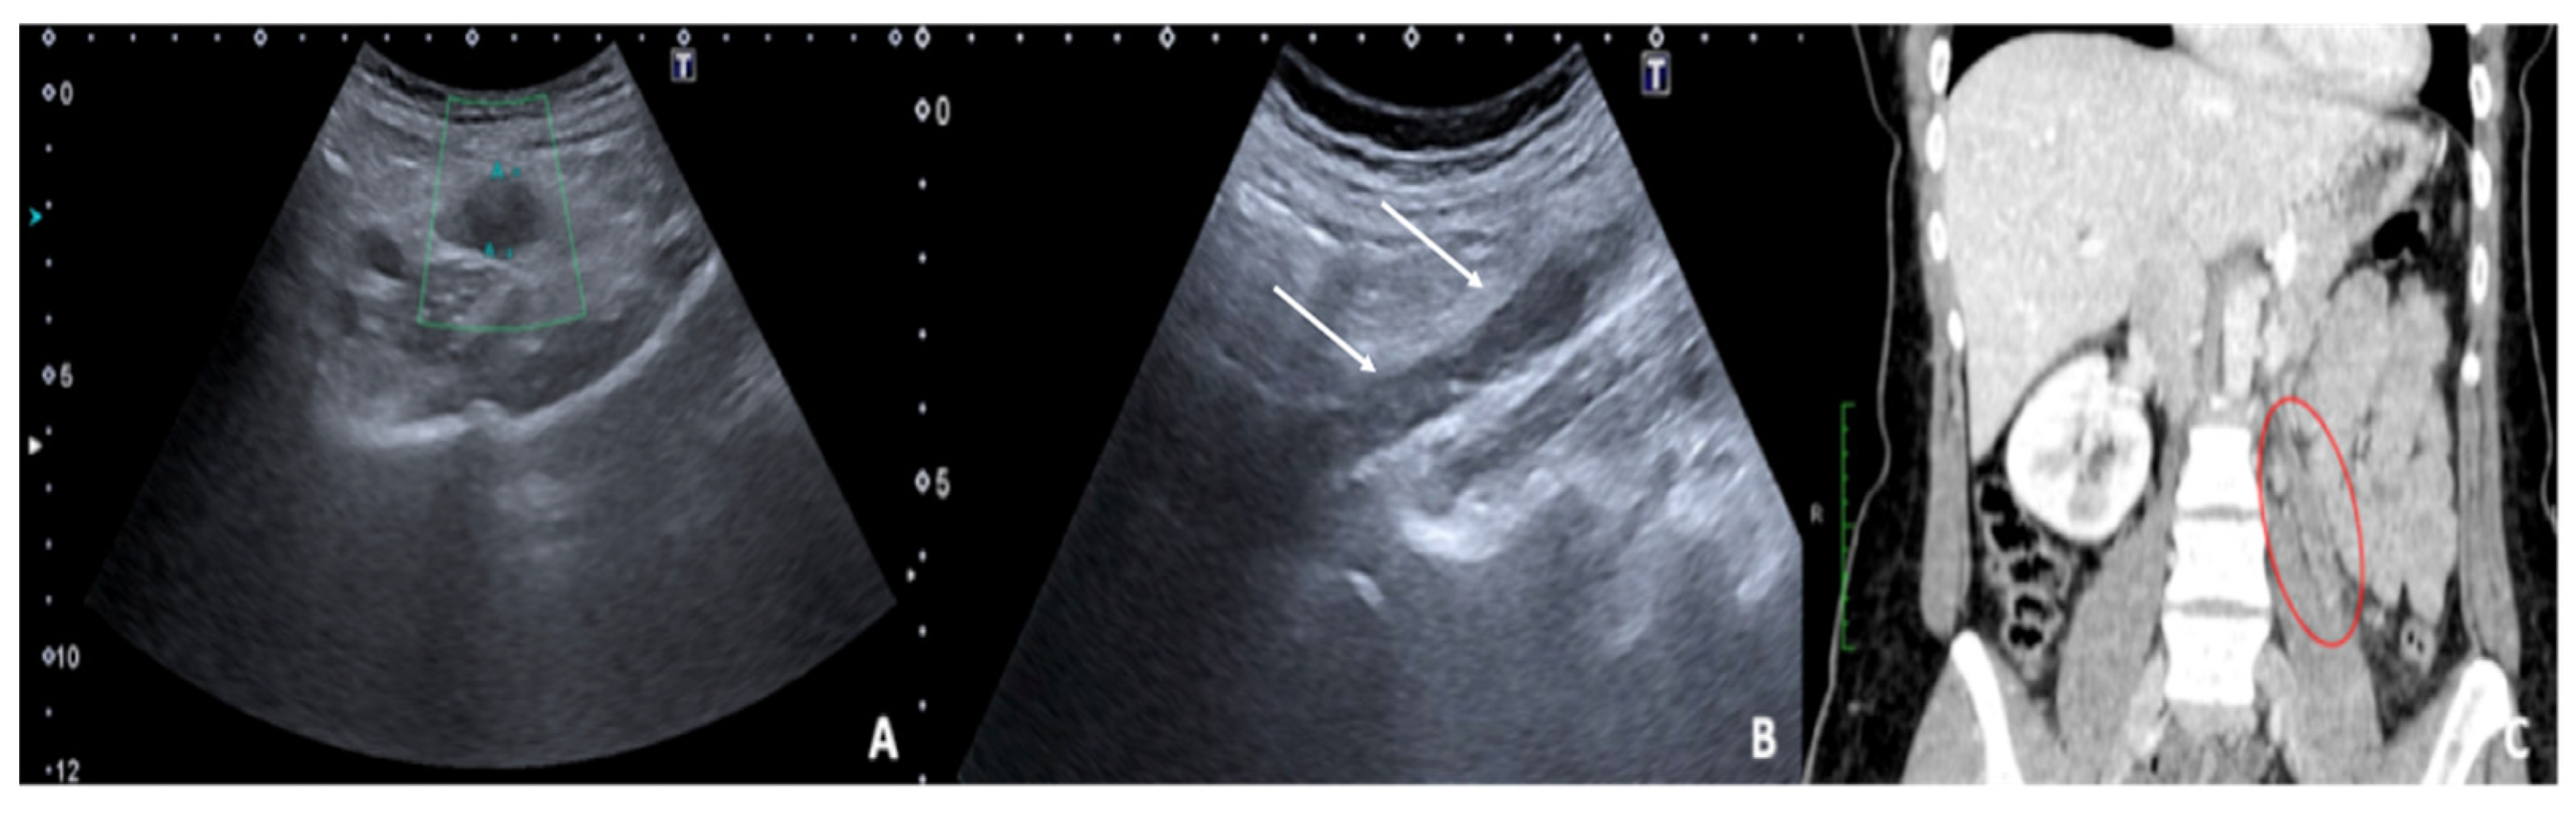

3.2. Ruptured or Bleeding Ovarian Cysts

Ovarian cysts are growths that develop in the ovaries during follicular maturation and are defined as functional cysts as they represent a physiological phenomenon related to ovarian function [1,6]. Functional ovarian cysts are caused by the overgrowth of a follicle due to the accumulation of fluid inside it, which is usually spontaneously reabsorbed without causing pain [6]. In some cases, they can rupture, releasing fluid into the peritoneal cavity, causing intense pain and bleeding complications. Haemorrhagic or ruptured ovarian cysts are common in women of reproductive age; however, the actual incidence is difficult to estimate, as many ruptured cysts are asymptomatic or found incidentally [7]. A broader estimate calculates about 7% of women worldwide experience a symptomatic cyst during their lifetime and in this event, US is the primary investigative tool [6,7,8]. The cyst may not be detectable if it has ruptured completely and decompressed; however, free fluid will generally be present in the pelvis. Therefore, rupture of ovarian cysts is often a diagnosis of exclusion when no other potential cause of the pain is identified [1,6,7,8]. The appearance of a haemorrhagic cyst detected by US is also variable and depends on the stage at which the patient has the scan. In the acute phase, it is possible to observe widespread homogeneous echoes with a fluid level and a dependent echogenic component represented by the blood sediment; over time, with the progressive degradation of haemoglobin, a reticular structure with internal echoes is observed (also described as a fishing net, spider web, or lace-like structure) (Figure 3) [1].

The fibrin bundles produce a network of precise linear echoes and are distinguishable from the real septa because they are numerous, thin, and dispersed, with an irregular structure and are not vascularised on colour Doppler US or contrast-enhanced US (CEUS) (Figure 4) [1].

In addition, unlike a true septum, they do not extend from one wall of the cyst to the other. The lack of flow detected by the colour Doppler imaging is an important feature, suggesting the presence of a mural thrombus rather than a tumour nodule. However, low levels of flow in solid tissue may not be detected by colour Doppler US, whereas contrast CEUS may optimise the diagnosis when clinical suspicion is present (Table 4) [1,6,7,8].

Figure 3. Haemorrhagic left ovarian cyst. Axial TSA-US image (a) shows a hemorrhagic corpus luteum ((a) caliper) with blood deposits ((a) arrows). On colour-Doppler imaging (b) circumferential blood flow is also shown.

Diagnostics 12 00939 g003

Figure 4. Haemorrhagic left ovarian cyst. Axial US image (a) shows a hemorrhagic cyst ((a) arrow) with reticular structure. On colour-Doppler imaging (b) there is no blood flow of the reticular structure. At follow-up (c) a complete resorption of the cyst is observed ((c) arrow).